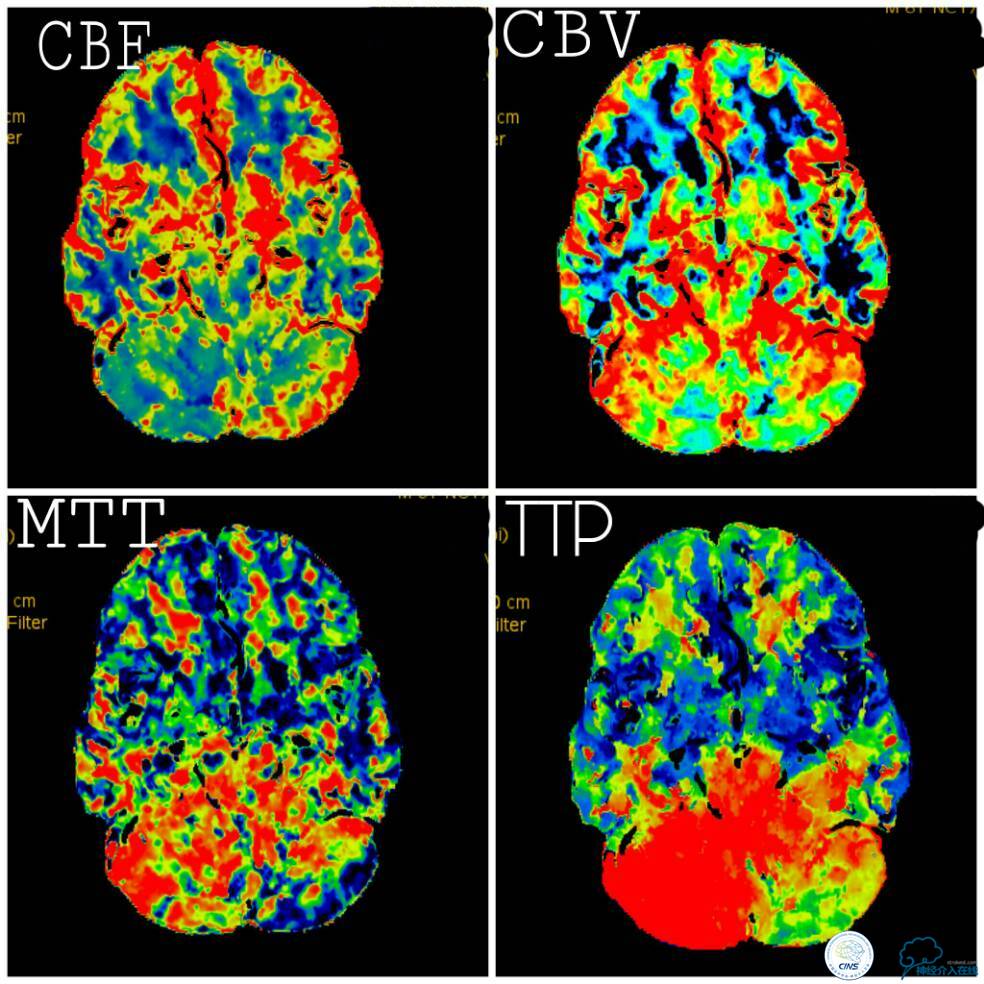

血栓弹力图检查:AA抑制率98.2%、ADP抑制率47.7%。颅内CTA及后循环CT灌注检查提示:右椎动脉V4段未见显影,左椎动脉与基底动脉汇合处重度狭窄,右椎动脉V4段在汇合点以下有显影(图5);双侧小脑半球低灌注,右侧为著(图6)。

图6